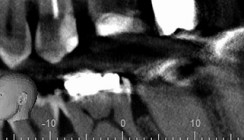

• 4. Sitzung am 18. Juni 2014: Kofferdam, Spülprotokoll: 30 Minuten NaOCl 5 %, EDTA 17 %, physiologische Kochsalzlösung, CHX 2 %. Trocknung. Analyse des Screenshots des DVT und Berechnen der Lage der Perforation. Die Perforation beginnt in ca. 17,2mm von der Schneidekante entfernt. Das Ausmaß der Osteolyse ist in sagittaler und vertikaler Richtung gut zu erkennen. Die Perforation ist knapp 2 mm groß in kaudal-apikaler Dimension (Abb. 6).

Auf den Röntgenaufnahmen zeigte sich eine kreisrunde Aufhellung im Kanalverlauf im Übergang vom mittleren zum apikalen Wurzeldrittel. Es wurde daher beschlossen, ein DVT anzufertigen (Größe 50 mm x 50 mm, Voxellänge 80 μm). Ergebnis: Es zeigte sich eine Diskontinuität im Wurzelverlauf auf der palatinalen Seite. Die Wurzelfüllung war unvollständig sowohl in kaudal-apikaler als auch in horizontaler Richtung. Die Perforation war ungefüllt. Der Knochen war auf der palatinalen Seite fast vollständig resorbiert (Abb. 4).